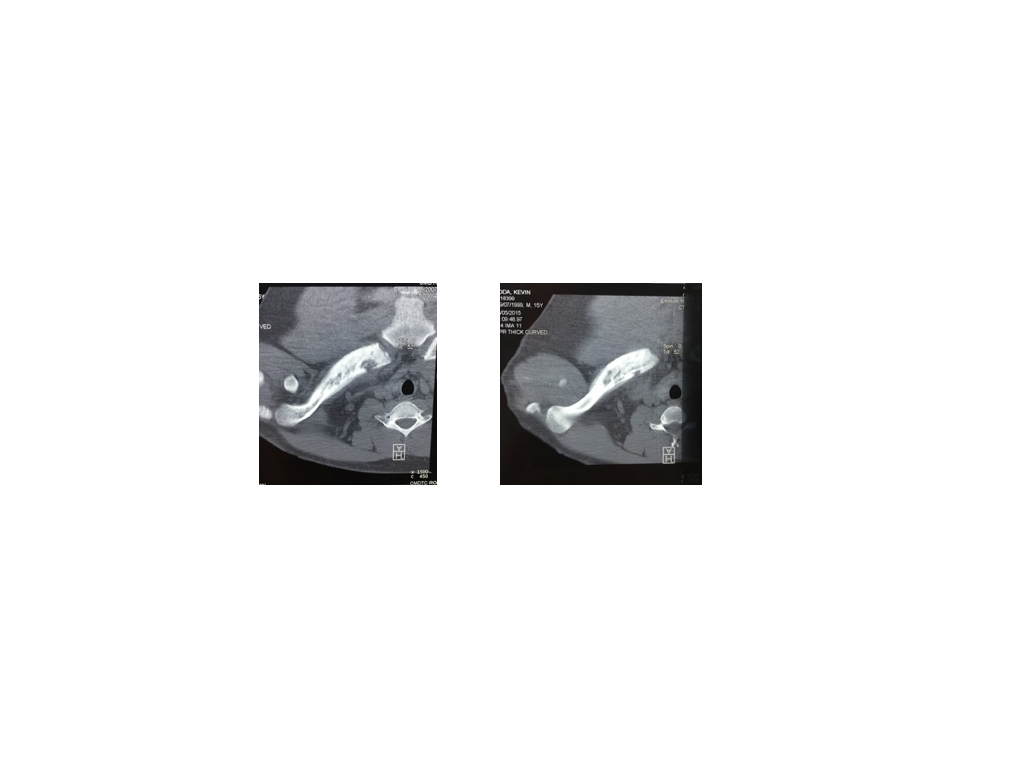

- Figura 3 tomografía

- Figura 3 tomografía computada